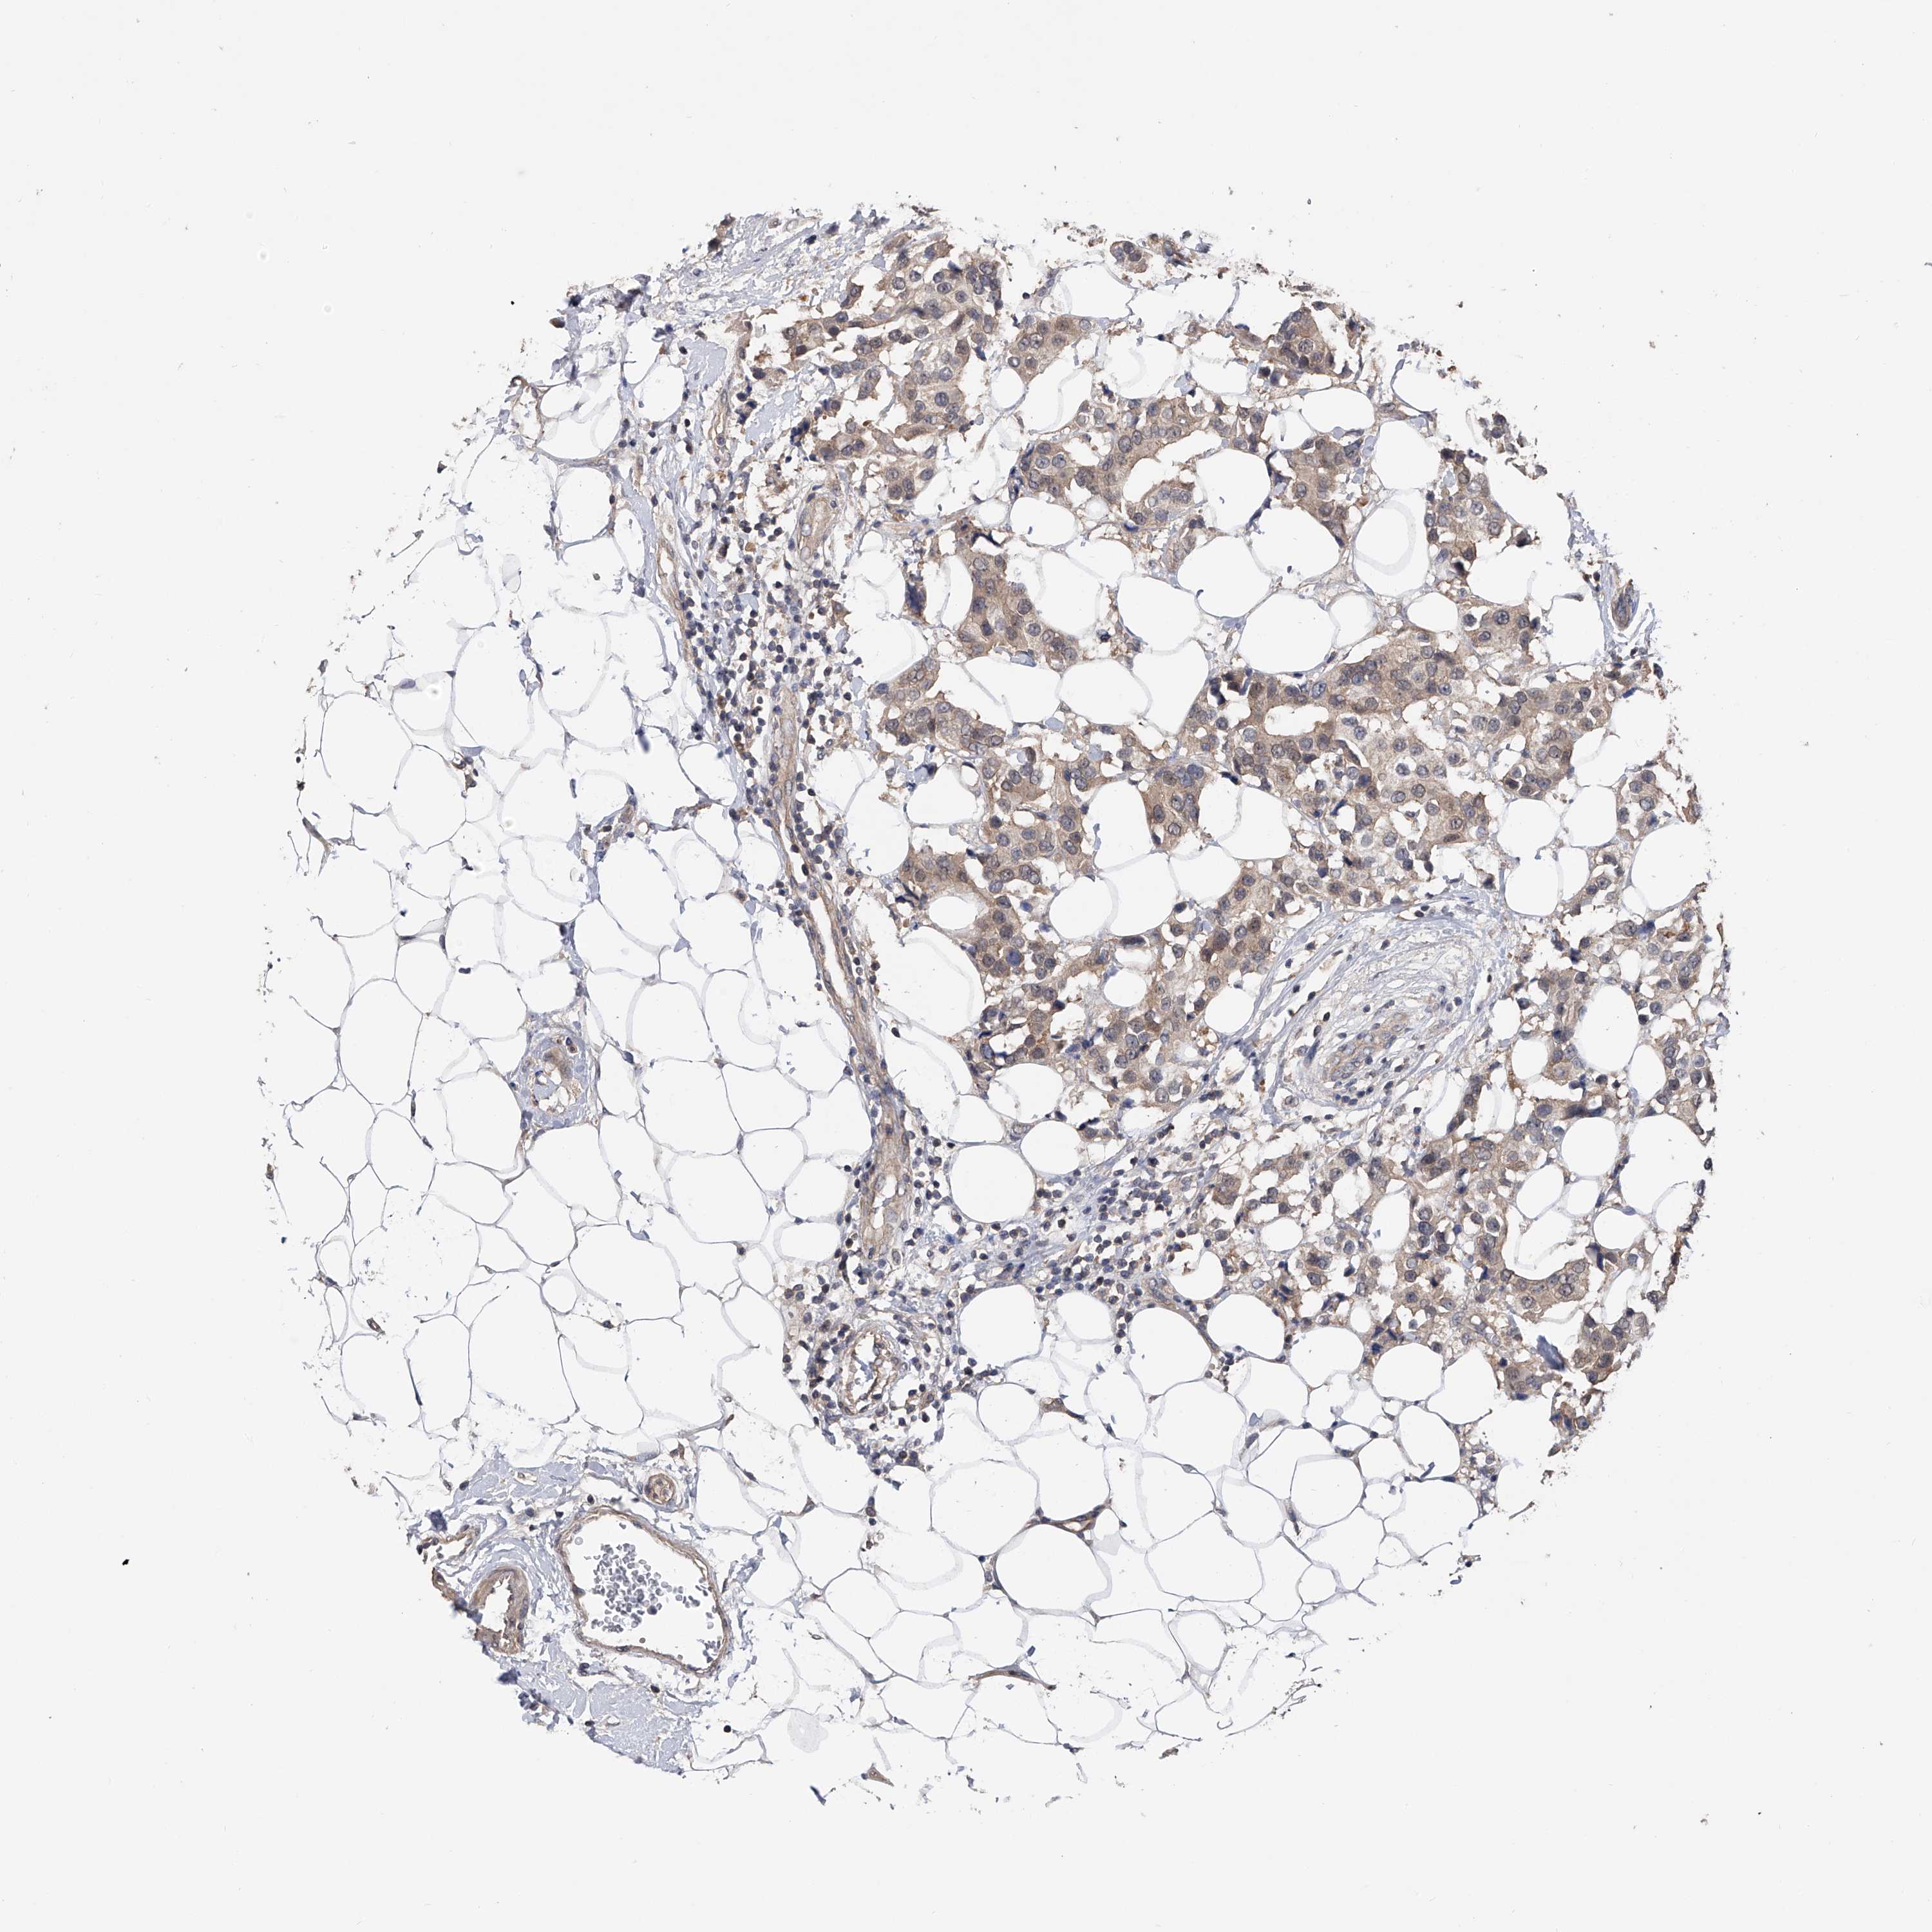

BRCA TCGA BRCA VALIDATION PROTEIN EXPRESSION

ANTIBODIES

AND

VALIDATION